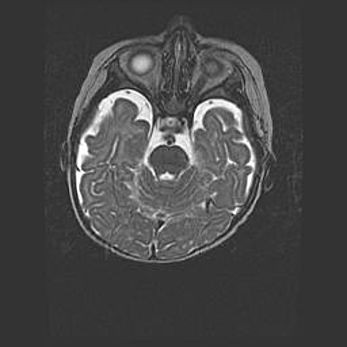

Наружная гидроцефалия с возможной атрофией височных областей.

Возраст: 28 дней

Вес: 3670 г

Пол: мужской

Окружность головы: 38 см

Срок гестации: 40 недель

Гидроцефалия головного мозга у новорожденных – это заболевание, которое характеризуется скоплением избыточного количества спинномозговой жидкости в желудочковой системе головного мозга в результате затруднения её перемещения от места выработки к месту поглощения в кровеносную систему или вследствие нарушения абсорбции. При открытой наружной форме гидроцефалии у новорожденных расширяются и переполняются субарахноидные пространства.

При нормотензивных  формах,  которые,  как  правило,  являются  следствием  перенесенных ишемических  повреждений  паренхимы  мозга,  возможно  сочетание микроцефалии  с нормотензивной гидроцефалией. В основе данных изменений лежит атрофия больших полушарий с преимущественной  локализацией  в  лобно-височных  областях.